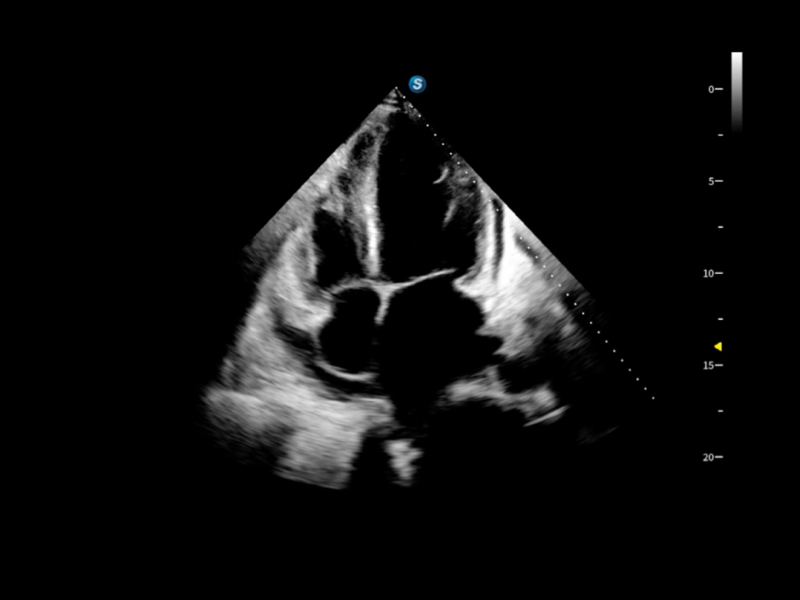

豐富的血流動(dòng)力學(xué)檢測(cè)技術(shù),可在不同醫(yī)療場(chǎng)景中高效捕捉血流信號(hào),助力臨床診療。

在傳統(tǒng)血流的基礎(chǔ)上優(yōu)化掃查和算法策略,能夠更好的抑制組織信息,提煉紅細(xì)胞運(yùn)動(dòng)信息,得到更高幀頻,高靈敏度和分辨率的血流信號(hào),還原更真實(shí)的血流動(dòng)力學(xué)。

通過光照模型,使二維血流顯示出立體的效果,增加血流的敏感性、成束性,減少外溢??梢院推渌煌难骷夹g(shù)聯(lián)合使用,融合不同技術(shù)的優(yōu)勢(shì)。輕松應(yīng)對(duì)微小血管,增強(qiáng)血流的立體效果,提升視覺敏感性。